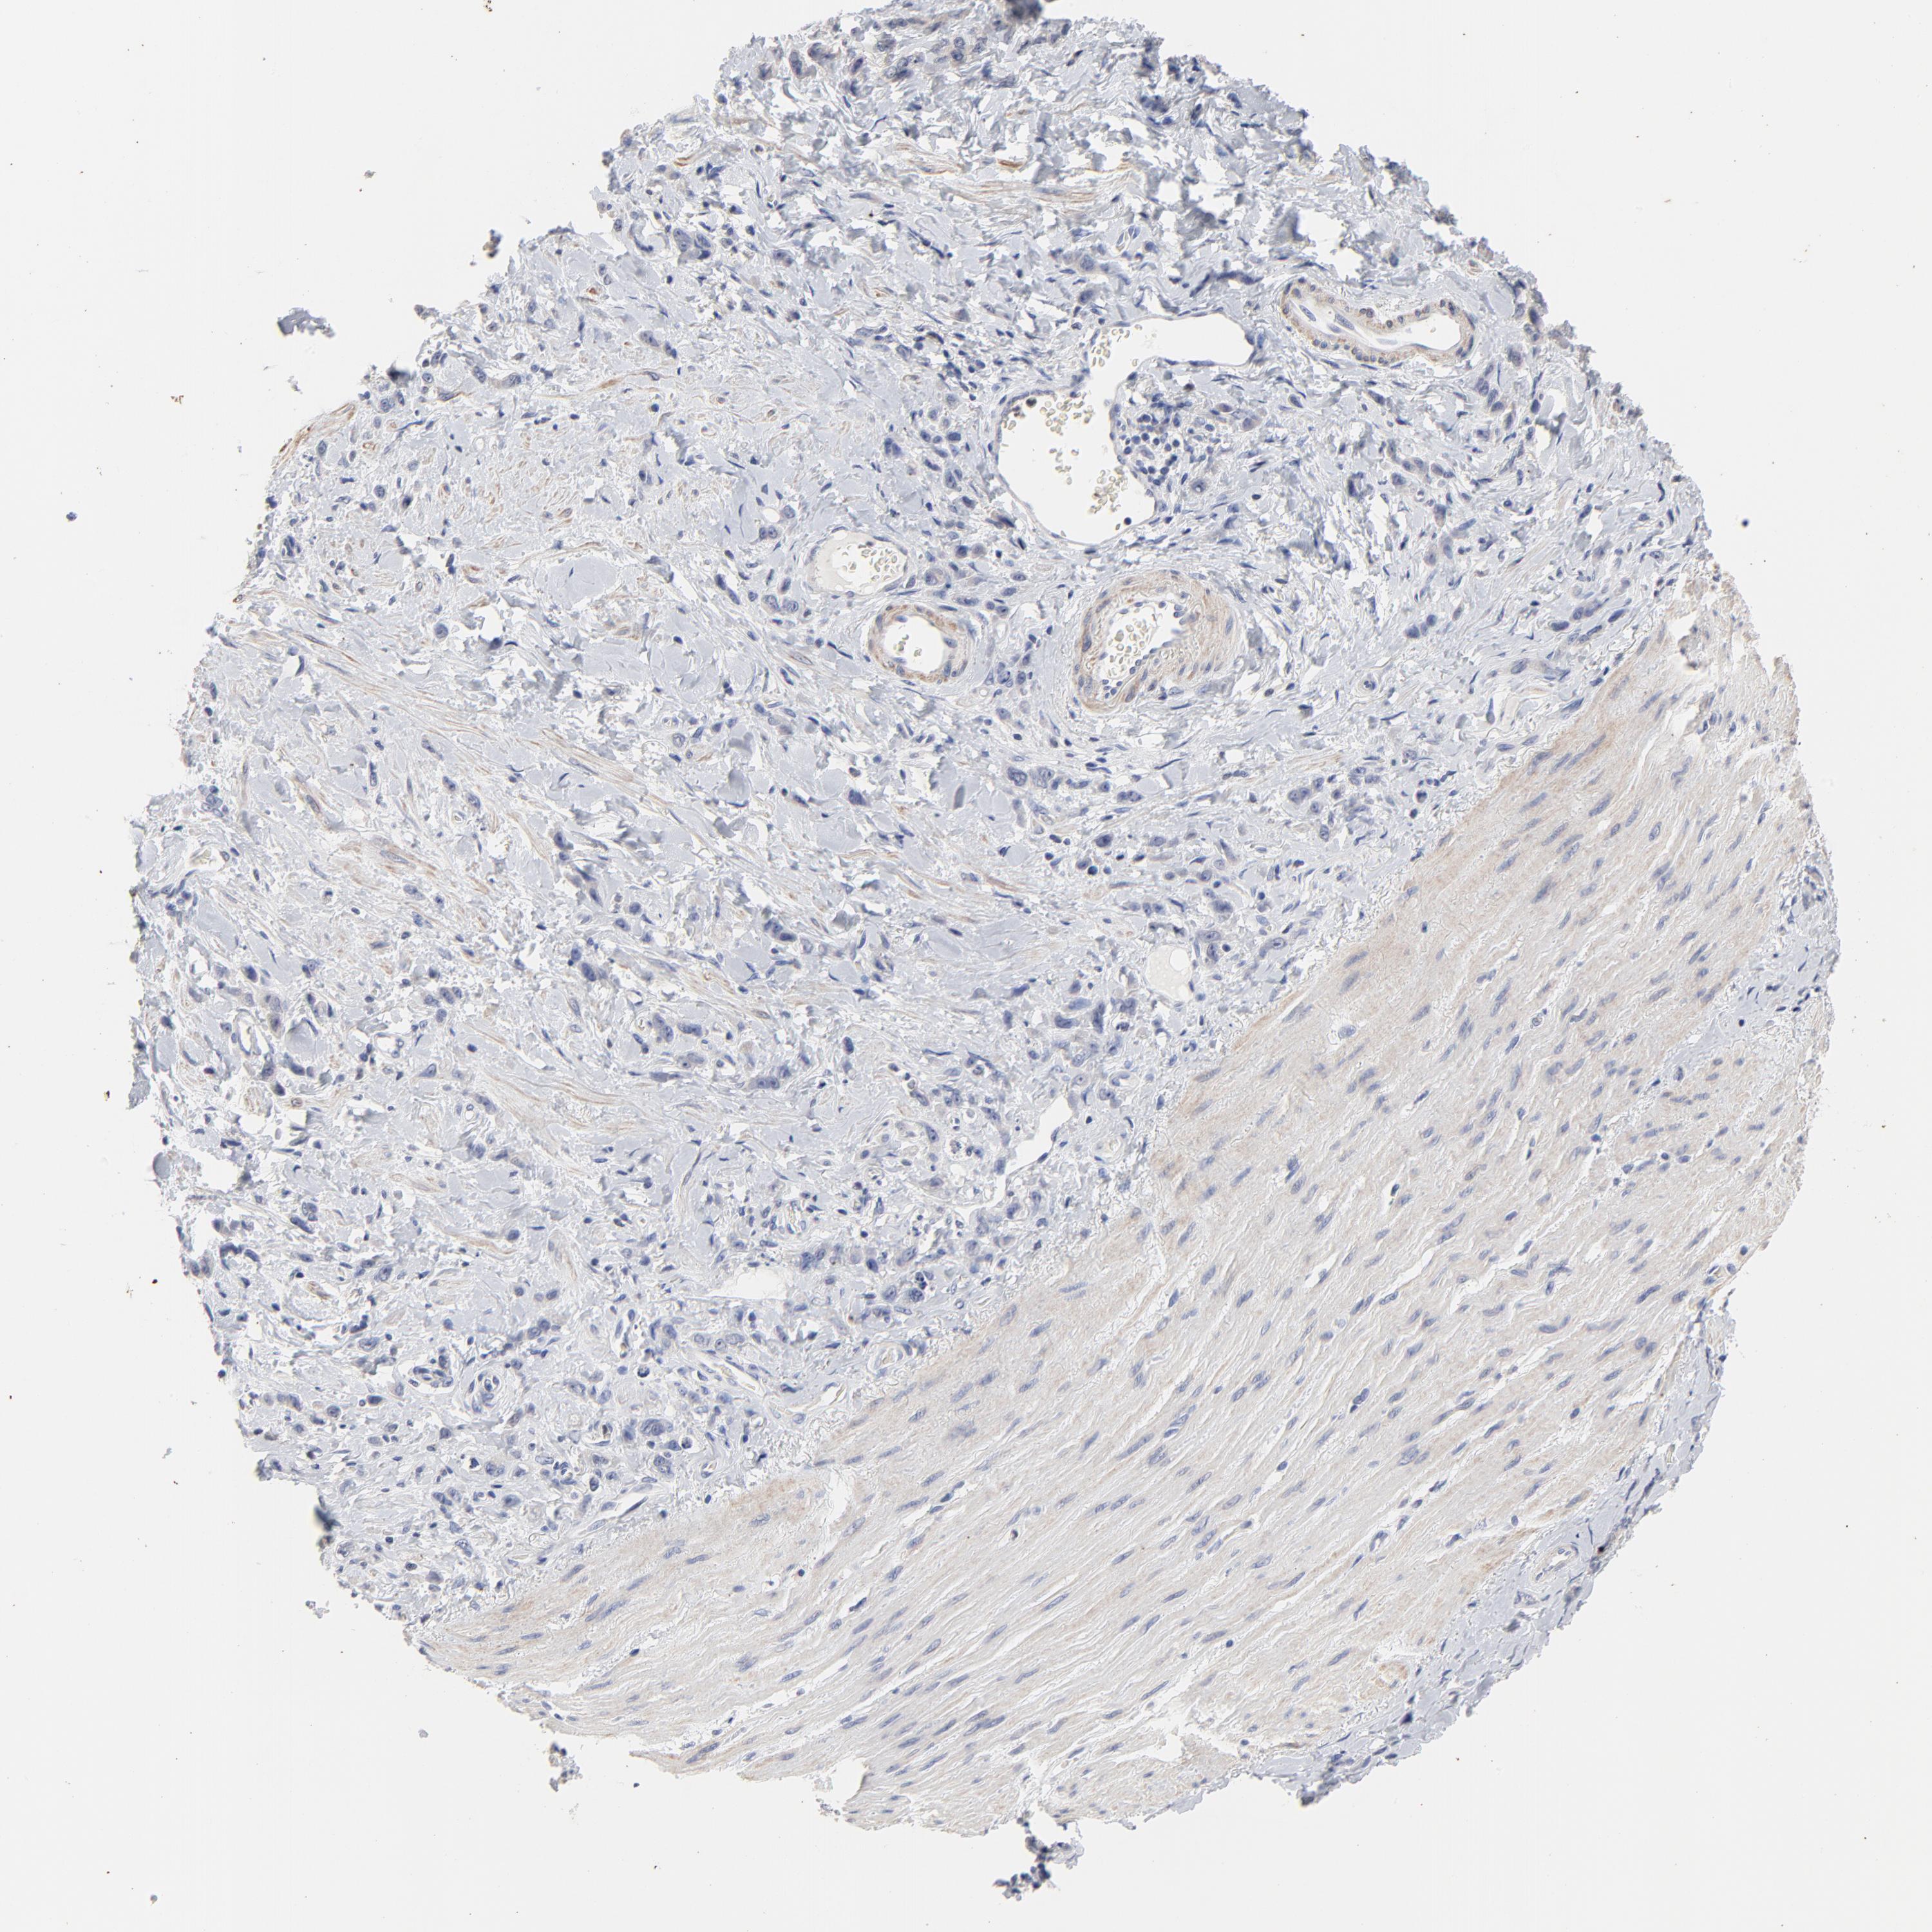

STOMACH CANCER - Protein expressioni

A mouse-over function shows sample information and annotation data. Click on an image to view it in a full screen mode. Samples can be filtered based on level of antibody staining by selecting one or several of the following categories: high, medium, low and not detected. The assay and annotation is described here.

Antibody stainingi

Antibody staining in the annotated cell types in the current human tissue is reported as not detected, low, medium, or high, based on conventional immunohistochemistry profiling in selected tissues. This score is based on the combination of the staining intensity and fraction of stained cells.

Each image is clickable and will lead to virtual microscopy that enables deeper exploration of all samples and also displays staining intensity scores, fraction scores and subcellular localization as well as patient and tissue information for each sample.

Antibody HPA002911

Staining

High

Medium

Low

Not detected

Intensity

Strong

Moderate

Weak

Negative

Quantity

>75%

75%-25%

<25%

None

Location

Nuclear

Cytoplasmic/membranous

Cytoplasmic/membranous,nuclear

Adenocarcinoma, NOS